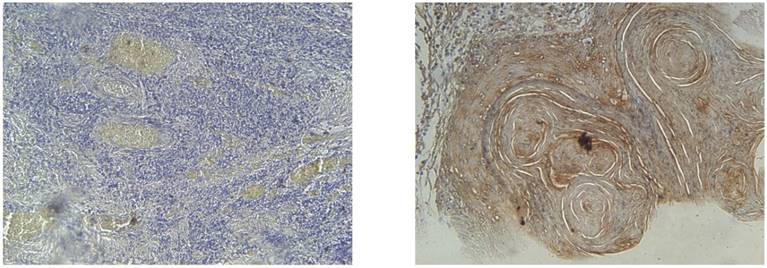

All slides were evaluated independently by two pathologists who were unaware of the clinical diagnosis to each other's evaluation. Any discrepancies arising between them were resolved using a conference microscope. To account for varying antigen expression within the tumour, 2-6 different visual fields were observed at 20x and 40x. EGFR positivity was expressed as membranous and/or cytoplasmic brown colour deposition. Scoring for EGFR expression was as follows: negative (<10% positive-stained cells), mild (10-20% positive-stained cells), moderate (20-60% positive-stained cells) and strong (>60% positive-stained cells).

IHC results for EGFR at magnification of 40x. EGFR negative (left) and EGFR strong positive (right) with >60% of cells showing membraneous and cytoplasmic staining